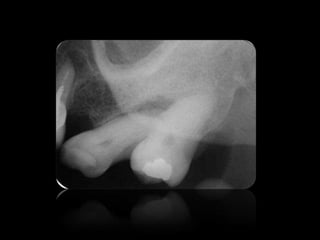

GEMINACIÓN